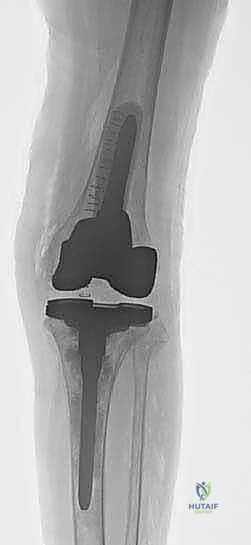

5. السيقان الممتدة (Intramedullary Stems)

في جميع حالات المراجعة تقريباً، لا يمكن الاعتماد فقط على الجزء العلوي من قصبة الساق للتثبيت بسبب ضعف العظم. لذلك، يتم استخدام مفاصل ذات "سيقان" معدنية طويلة تمتد داخل القناة النخاعية لعظم قصبة الساق (Diaphysis). تقوم هذه السيقان بنقل الضغط والوزن من المنطقة الضعيفة في الأعلى إلى العظم القوي في الأسفل، مما يحمي المنطقة المعاد بناؤها ويضمن استقرار المفصل.

الخطوة الخامسة: زراعة المفصل المراجع الجديد

يتم إدخال المكون الظنبوبي الجديد (Tibial Tray) مع الساق الممتدة (Stem) التي تدخل في القناة النخاعية. يتم تثبيت هذه الأجزاء إما بالضغط الميكانيكي (Press-fit) أو باستخدام الإسمنت العظمي في مناطق محددة. يتم تكرار نفس العملية لعظم الفخذ إذا لزم الأمر.